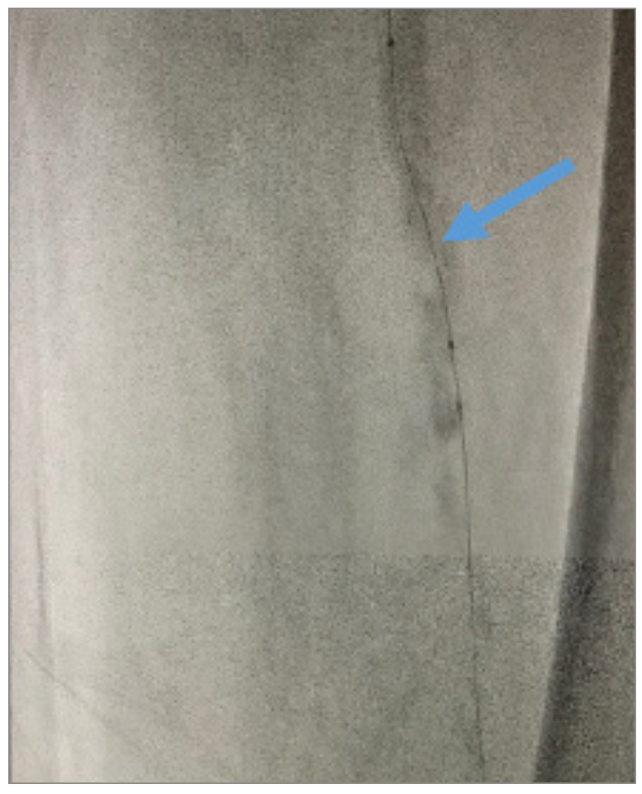

Angiography revealed that the superficial femoral artery (SFA) was occluded in the proximal segment with a short nub (Figure 1) and reconstituted in the mid segment by the profunda collaterals (Figure 2), before becoming reoccluded shortly thereafter and reconstituting in the distal SFA by the profunda collaterals (Figure 3). The P1 and P2 segments of the popliteal artery were patent, but the P3 segment had a short occlusion. The posterior tibial artery and peroneal artery also were patent.